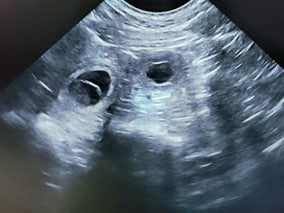

The Role of Dog Pregnancy X-rays

Dog pregnancy X-rays are invaluable tools for breeders and veterinarians in monitoring the health and development of pregnant dogs and their offspring. Here we explore the significance of dog pregnancy X-rays, their role in veterinary care, and introduce innovative solutions like Bellylabs - the first-ever at-home dog pregnancy test - to enhance the breeding experience.